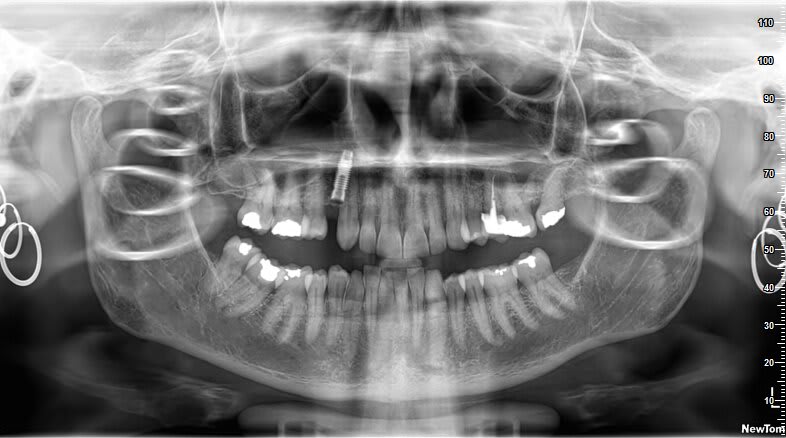

Reconnaitrais tu cet implant posé en france il y a 29-30 ans ?

Rétro stp sans plus de précision (finesse de la radio) j'ai environ 600 correspondances.....

Screw vent?

Ça ressemble au niveau connectivité hexagonale, et au niveau du col.

Il y a 30 ans, on avait moins de systèmes implantaires aussi...

Merci pour ta réponse, le soucis est qu'avec une rétro j'ai du mal à avoir "l'apex" de l'implant, je vais dire à la patiente de repasser.